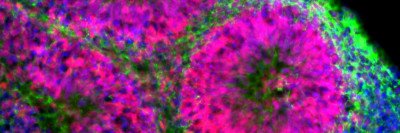

Seeing the Light: How Engineered Nerve Cells Might Curb Parkinson’s Disease

A new tool called optogenetics is revealing clues about the function of a promising experimental therapy derived from stem cells.

In the Lab

Genetic “Kill Switch” Could Make Cell Therapies Safer

Researchers have engineered a gene into therapeutic cells that allows them to turn off tumor growth if some of the cells become cancerous.

Human Stem Cells Treat Parkinson’s in Mice

New research published in Nature by Sloan Kettering Institute developmental biologist Lorenz Studer describes how stem cells from human embryos were us...

Novel Stem Cell Technique Shows Promise in Treating Disease

Cell replacement therapy seeks to restore function in the body by replacing cells that are lost due to disease or injury with new, healthy cells. One disease for which this type of therapy holds particular promise is the degenerative neurological disorder Parkinson’s disease, which is characterized by symptoms related to movement.

Therapeutic Cloning Treats Parkinson's Disease in Mice

Research led by investigators at Memorial Sloan Kettering Cancer Center has shown that therapeutic cloning, also known as somatic-cell nuclear transfer (SCNT), can be used to treat Parkinson's disease in mice.

Research Shows Therapeutic Cloning Can Cure Parkinson's-like Disease in Mice

NEW YORK, September 21, 2003 - New research from Memorial Sloan Kettering Cancer Center (MSKCC), Cornell University, and The University of Connecticut describes a novel way of producing therapeutic nerve cells that can cure mice with Parkinson's-like disease. The work, which will be published in the October issue of Nature Biotechnology (available online September 21), provides the first evidence that cloned cells can cure disease in an animal model.